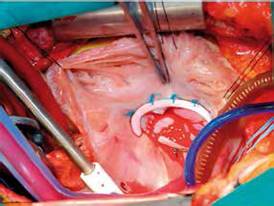

En 1971 Alain Carpentier comunica la utilización de un anillo rígido destinado a reducir la dilatación anular, permitiendo así corregir la insuficiencia tricuspídea. En los siguientes treinta años se emplean con esta finalidad bandas de teflón, así como anillos rígidos, semirrígidos o flexibles; biodegradables (polímero de poli-1,4-dioxanona, que se implanta dentro del anillo nativo para promover la inflamación y su transformación secundaria en tejido fibroso); completos o parciales. Debe determinarse el tamaño del anillo a las valvas y a la superficie corporal; las suturas deben ser puestas en el anillo a 1-2 mm del borde de los velos, con precaución de no lesionar el anillo aórtico adyacente y la arteria coronaria derecha, además de evitar dañar el haz de His en la mitad de la porción septal del anillo. La dehiscencia en anillos rígidos es una complicación tardía potencial9. En la Figura 4 se observa el resultado final de un anillo flexible parcial con coaptación total de las valvas tricúspideas.

Fotografía transoperatoria: resultado final de anuloplastía tricuspídea con anillo, donde se aprecia coaptación total de las valvas. Tomado deBahamondes J C. Rev Med Clin. Condes. 2022; 33 (3) 235-246.

Figura 4: ANULOPLASTÍA TRICUSPÍDEA CON ANILLO PROTÉSICO

Desde el año 2002, al evidenciar que en los pacientes con dilatación significativa del ventrículo derecho no es suficiente la anuloplastía para evitar la IT residual progresiva, se postula la utilización de un anillo parcial de forma elíptica tridimensional (Edwards MC3). Como en la IT severa el anillo tricuspídeo al dilatarse se aplana, y todo su contorno queda en un mismo plano en el espacio y se convierte en circular, la anuloplastía puede no ser suficiente para evitar recidiva regurgitante, pero parece que, utilizando este nuevo anillo, disminuye notoriamente la recurrencia y la morbimortalidad3,10.